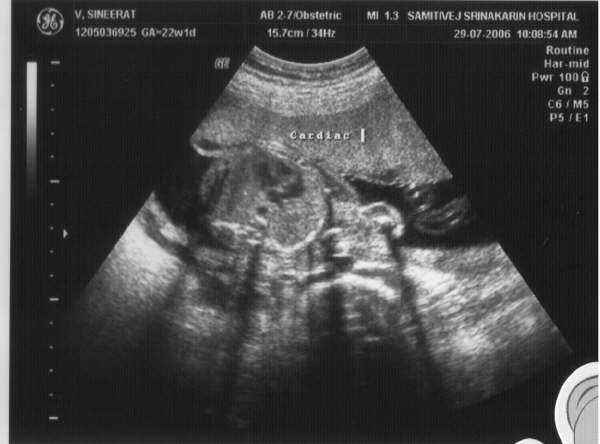

6:00pm, we checked in to our camp. It’s quite comfortable like hotel room although it is in tent style. Some groups start the next activity to drive ATV car into the corn field which is the last program before dinner. For me, I passed this one since my wife is still pregnant and need to take care for my son.